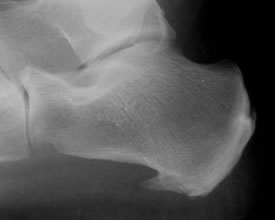

The plantar calcaneal (Heel) spur has been described as a bone outgrowth just in front of the medial tuberosity of the calcaneus.

These heel spurs are often seen on ultrasound or xray and are sometimes blamed for heel pain.